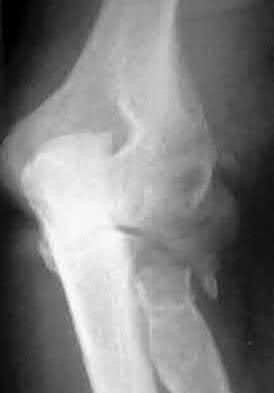

A 51-year-old carpenter presents with a distal humerus nonunion (Figures A and B). After repair of the nonunion, he is lost to follow up for 3 months and then presents to your clinic pain-free and with evidence of fracture union. On examination the elbow arc of motion is 10-80 degrees. Following a brief failed trial of conservative management, you recommend:

Limited flexion outside a functional range of motion (30-130 degrees) can be quite debilitating, and it is often addressed with open release of the posterior bundle of the MCL and posterior capsule and excision of osteophytes.

A frequent complication of distal humerus fractures is post-traumatic stiffness. This patient has had multiple procedures about the distal humerus, and the question stem implies that he did not complete a structured range of motion protocol following the repair of his nonunion. Beyond a trial of conservative management, there are many techniques described for capsule and soft tissue releases as well as bony resections if heterotopic ossification is present. This patient's severely limited flexion would best be addressed with a release of the posterior bundle of the MCL, and with flexion

Figures A and B show a AO/OTA type C2 intraarticular distal humerus fracture. Figure C is a coronal CT scan showing intraarticular comminution. Illustration A shows fixation of the fracture with bicolumnar plating through an olecranon osteotomy approach. Illustration B shows the various approaches to the distal humerus (left, Campbell triceps splitting; center left, O'Driscoll triceps reflecting anconeus pedicle; center right, Bryan-Morrey approach, leaving the triceps attached laterally to the fasciocutaneous flap, but elevating it off the ulna; right, olecranon osteotomy). Illustration C shows 3 methods of olecranon osteotomy (A and B, Intra-articular transverse; C-F, Extra-articular oblique; G, Intra-articular chevron).